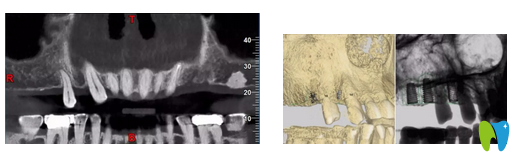

CT片顯示14區(qū)缺牙間隙較狹窄

CBCT顯示:14區(qū)缺牙間隙較狹窄,模擬植入后,近遠(yuǎn)中距臨牙安 全距離不足1.5mm;其余缺牙區(qū)骨質(zhì)及骨量的情況,以及距離上頜竇底高度均基本滿足種植要求。缺牙區(qū)咬合高度基本滿足后期修復(fù)要求。

▲ 患者口內(nèi)3D圖拍攝